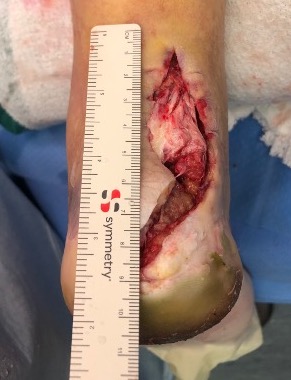

Complications

Nerve injury / numbness / posterior heel pain

Wound infection / wound breakdown

Tendoachilles rupture

Rupture of the achilles tendon insertion after open debridement and repair

Salvage with turndown and FHL transfer